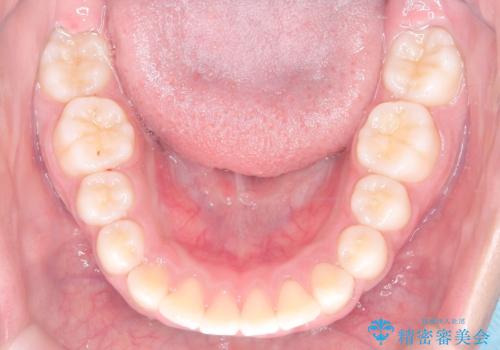

- 患者様は前歯の突出を主訴に来院されました。診査の結果、上顎の前歯が前方に傾斜しており、口元がやや突出して見える状態でした。一般的にこのようなケースでは抜歯矯正が選択肢となりますが、**患者様が抜歯を希望されなかったため、非抜歯での遠心移動(奥へ動かす治療)を計画しました。そのため、リンガルアーチ(歯の裏側に装着する装置)とTAD(歯科矯正用アンカースクリュー)**を併用し、上顎の歯を後方へ移動させながら噛み合わせを整える方法を選択しました。

まず、上顎にリンガルアーチを装着し、歯列の幅を適正に維持しながら遠心移動をサポート。さらに、**TAD(矯正用アンカースクリュー)**を利用することで、奥歯を固定源とせずに前歯だけを後方へ移動させることが可能になりました。これにより、抜歯をせずに前歯の突出を抑え、バランスの取れた口元へと改善。治療後、患者様からは「抜歯せずに理想の仕上がりになり、大満足」とのお声をいただきました。